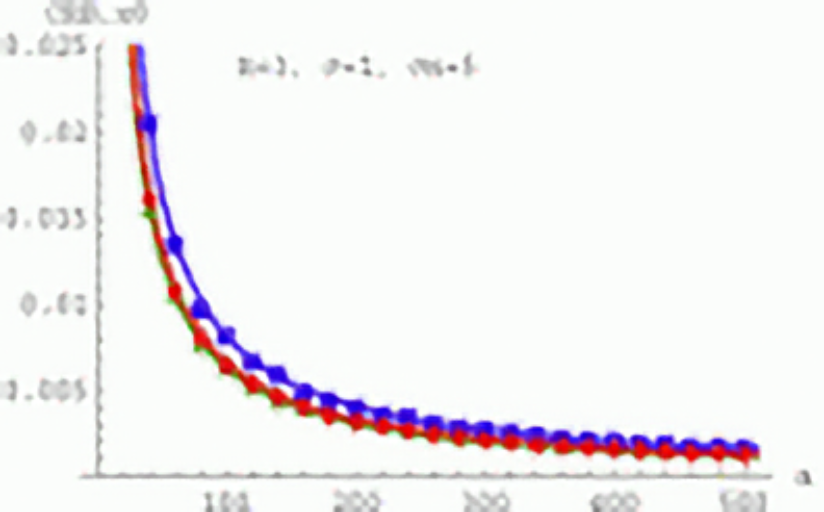

Investigation of theoretical limits for the precision of feature and landmark localization. Derivation of analytic lower bounds (Cramér-Rao lower bounds).